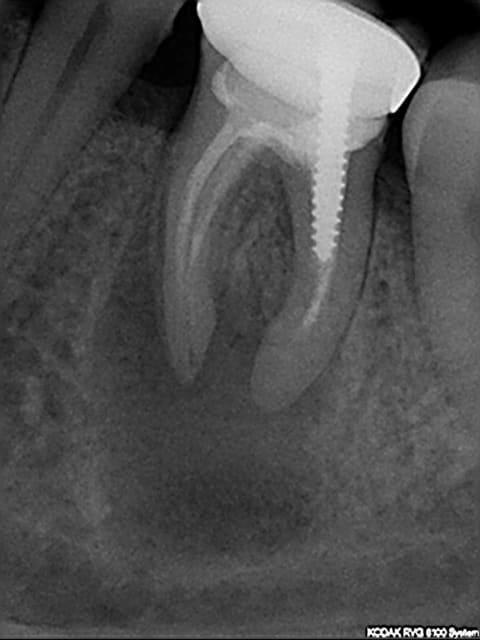

Voici un cas qui ressemble un peu au tien:

reprise de traitement puis resection apicale et comblement.

A 1 an , aucun signes cliniques et on surveille.